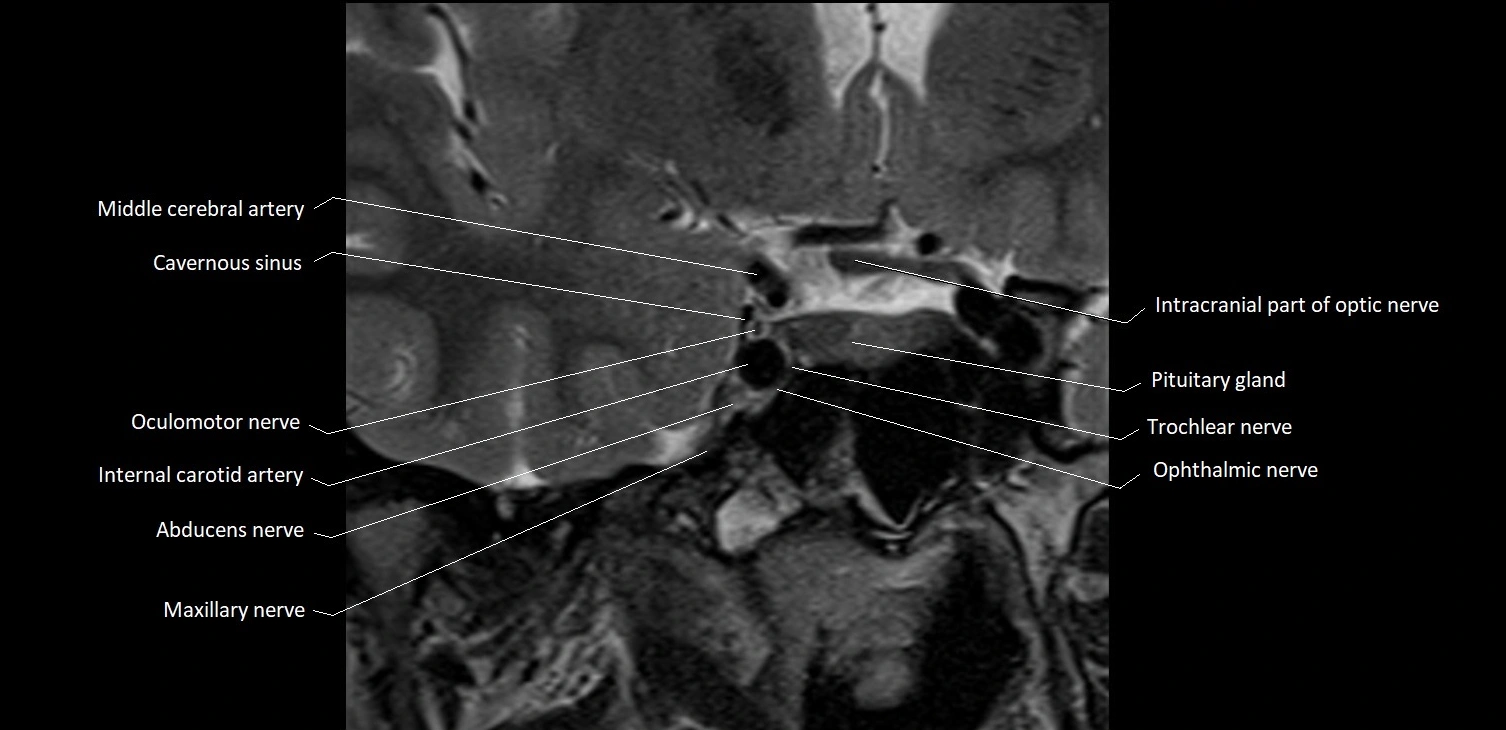

MRI Appearance

The abducens nerve is a small, thin, linear structure

Best visualized on high-resolution T2-weighted 3D MRI sequences (e.g., FIESTA or CISS)

Seen as a hypointense (dark) line running from the brainstem at the pontomedullary junction, traversing the prepontine cistern, and entering Dorello’s canal under the petrosphenoidal ligament, then into the cavernous sinus, and finally the orbit

May be challenging to visualize in standard MRI due to its small size

Pathology may be inferred by absence, displacement, or enhancement of the nerve

MRI images